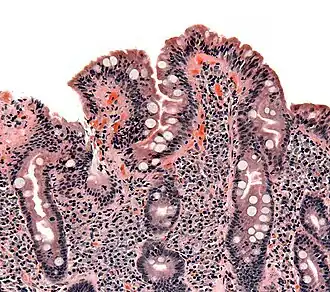

Geralmente é realizada uma biópsia do duodeno ou do jejuno. São recolhidas entre quatro e oito amostras de tecido, já que as áreas podem não ser afetadas por igual e se a amostra for recolhida a partir de uma área saudável pode dar origem a falsos negativos.[39]

Na maior parte das pessoas com doença celíaca, o intestino delgado apresenta-se normal durante uma endoscopia. No entanto, existem cinco observações endoscópicas que sugerem doença celíaca: pregas mucosas serrilhadas, padrão em mosaico da mucosa (semelhante ao padrão de lama seca), proeminência dos vasos sanguíneos da submucosa e padrão nodular da mucosa.[67]

As alterações patológicas clássicas da doença celíaca no intestino delgado são categorizadas de acordo com a Classificação de Marsh:[69][70]

- Estádio 0: mucosa normal

- Estádio 1: infiltração linfocitária intraepitelial superior a 20 por cada 100 enterócitos

- Estádio 2: proliferação das criptas intestinais

- Estádio 3: atrofia parcial ou total das vilosidades intestinais e hipertrofia das criptas[71]

- Estádio 4: hipoplasia da constituição do intestino delgado

A classificação de Marsh, introduzida em 1992, foi posteriormente modificada em 1999 para seis estádios, tendo o estádio 3 sido dividido em três sub-estágios.[72] Os estudos posteriores demonstraram que este sistema nem sempre era fidedigno e que as alterações observadas na doença celíaca podiam ser descritas em um de três estágios — A, B1 e B2 — em que A representa a infiltração linfocitária com aparência das vilosidades normal e em que B1 e B2 descrevem a atrofia parcial ou total das vilosidades.[34][73]